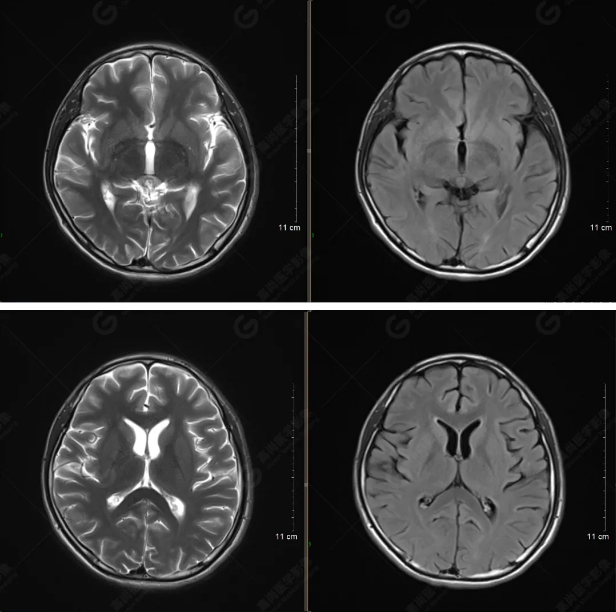

以下是T1WI軸位掃描及矢狀位掃描:

雙側(cè)大腦半球?qū)ΨQ,灰白質(zhì)對比正常,顱內(nèi)未見異常信號影。腦室系統(tǒng)未見擴(kuò)大,中線結(jié)構(gòu)居中。腦溝、裂未見增寬。幕下小腦、腦干未見異常。矢狀位示垂體形態(tài)、大小級信號未見異常。所示左側(cè)乳突內(nèi)見多發(fā)短T1長T2信號影。

顱腦MRI平掃未見明顯異常,左側(cè)乳突內(nèi)積血,建議補充SWI檢查。